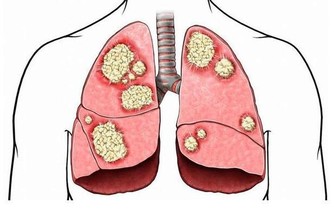

腎貯藏精氣,為人體生殖、造血、生長發育、防衛病邪的基礎物質,平衡身體水液代謝,與膀胱合作排泄尿液,負責納氣,協調呼吸運動,主骨生髓,養腦益智,促進頭髮生長,腎氣通耳,控制聽力,控制二陰的開合。

為了維護身體健康,平時就要做好腎臟的保護工作。盡量的少吸煙喝酒,每天堅持多喝水,多鍛煉身體。再試試這些養腎的方法